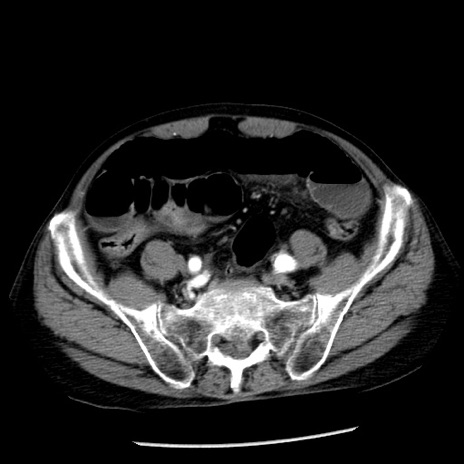

冠状断像

【症例】80歳代男性

【主訴】嘔吐

【現病歴】昨晩2回嘔吐あり、今朝になっても嘔吐あり。来院。

【既往歴】胃潰瘍

【身体所見】意識清明、BT 37.6℃、BP 166/95mmHg、HR 100bpm、SpO2 97%、腹部:平坦・軟、腸蠕動音聴取良好、圧痛なし。

【データ】WBC 21900、CRP 1.46